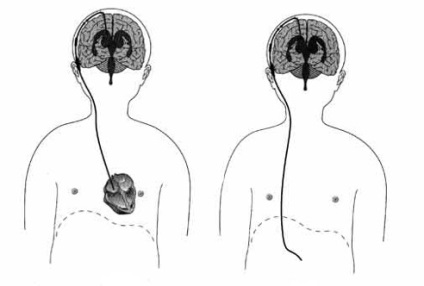

A lényege a művelet, hogy a beállított ventriculo peritoneális sönt amely eltereli a felesleges cerebrospinális folyadék a hasüregben. A sönt három részből áll:

- ventrikuláris katéteren;

- szelep;

- peritoneális katétert.

Ventrikuláris katéteren - egy rugalmas, üreges cső nyílásokat a belépési italt benne található az agy kamrák nyomás alatt. További liquor belép a szelepet. Modern szelepek különböző átviteli sebességű likőr, amely lehetővé teszi megfigyeljük az idegsebészeti, hogy ellenőrizzék a folyadék térfogata tompított a szelepen keresztül.

Ventriculo-peritoneális sönt legelőnyösebb műveletet egy agy hydrocephalus. Maga a beavatkozás több szintből áll:

- Szúrja és vízelvezető az oldalsó agykamra, pontosabban - Front kürt.

- Az orvos határozza meg az előre kiegyenlített söntrendszerként.

- Szubkután tartott kardioperitonealny katéter.

- A katéter távolabbi merítjük a hasüregbe.

- Ellenőrizte a rendszer működéséhez.

- Úgy hajtjuk elvarrásba sebek.